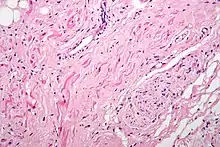

H&E stained fibers of the vagus nerve (bottom right) innervate the sinoatrial node tissue (middle left)

Parasympathetic innervation of the heart is partially controlled by the vagus nerve and is shared by the thoracic ganglia. Vagal and spinal ganglionic nerves mediate the lowering of the heart rate. The right vagus branch innervates the sinoatrial node. In healthy people, parasympathetic tone from these sources is well-matched to sympathetic tone. Hyperstimulation of parasympathetic influence promotes bradyarrhythmias. When hyperstimulated, the left vagal branch predisposes the heart to conduction block at the atrioventricular node.